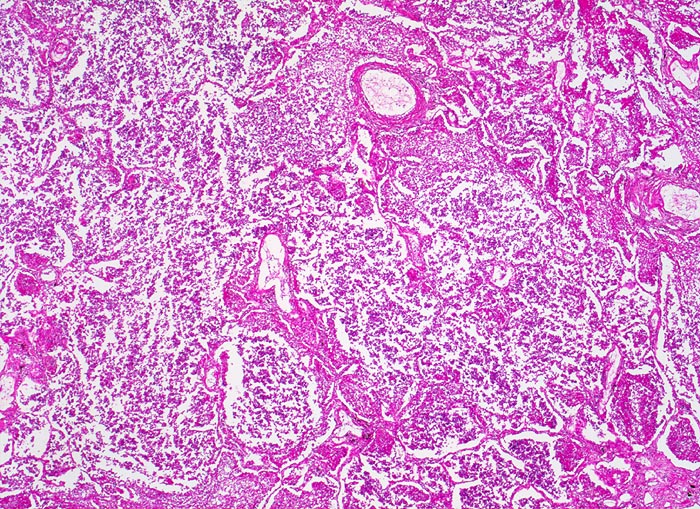

Lobärpneumonie

Alle Alveolen sind gleichmässig und diffus befallen und im selben Stadium der Entzündung. Sie sind angefüllt mit fädigem Fibrin und neutrophilen Granulozyten.

Eine Lobärpneumonie tritt auf, wenn die Erreger die Alveolarräume so ausgedehnt und rasch befallen, daß sie erst vor anatomischen Grenzen (z.B. einem Lappenspalt) Halt machen.